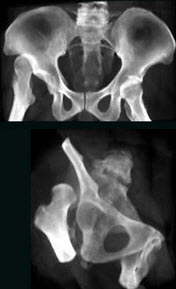

175、单项选择题

男,32岁,因车祸致右髋关节肿痛,活动受限摄片如图示,最可能的诊断是()

A.骨盆Ⅰ型骨折

B.骨盆Ⅱ型骨折

C.骨盆Ⅲ型骨折

D.骨盆Ⅳ型骨折

E.以上均不是